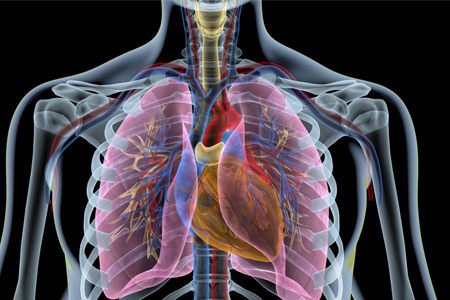

肺癌是全球範圍内最常見的惡性腫瘤之一,對患者生命質量和健康狀況造成了嚴重威脅。随着醫學科技的不斷發展,肺癌治療手段也在不斷改進和優化。